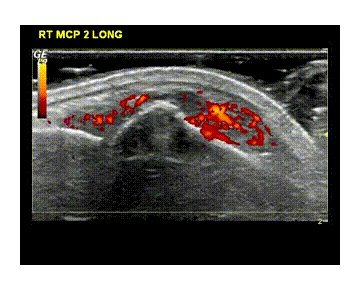

The development of a prospective early arthritis cohort with high quality clinical and imaging data (state-of-the-art 3D/4D ultrasound-US / power-Doppler-PDU imaging) together with a comprehensive collection of biological samples (blood, urine and synovial tissue) will provide a unique resource to search for early predictors of disease evolution as well as to enable early proof of concept/mechanistic studies with stratified entry according to the imaging and immunological profile. Thus, this cohort will represent an ideal platform for clinical trials of novel substances. In particular, it is envisaged that time integrated US/PDU imaging will improve on currently employed composite clinical assessment tools permitting earlier evaluation of response to therapy and development of prognostic algorithms of structural damage progression. Equally, the comprehensive collection of samples (particularly synovial tissue through a US guided minimally invasive biopsy) will enable scientists to test and generate hypotheses on the disease origin, natural course and response to treatment.